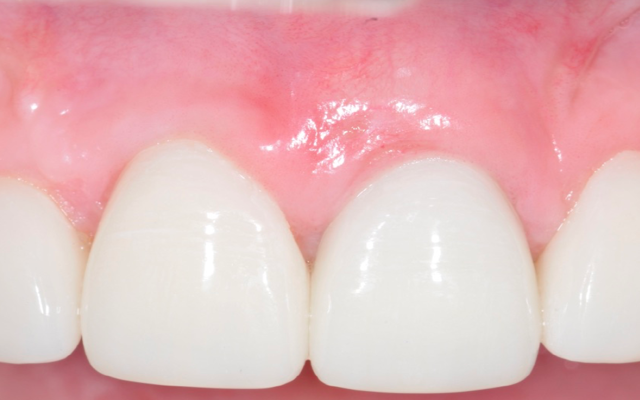

Gum grafting on teeth is a periodontal surgical procedure where the patient’s own gum is repositioned upward (Figure 12A-12B) or if the gum is thin or receded (Figure C), extra gum can be harvested from the roof of the mouth.